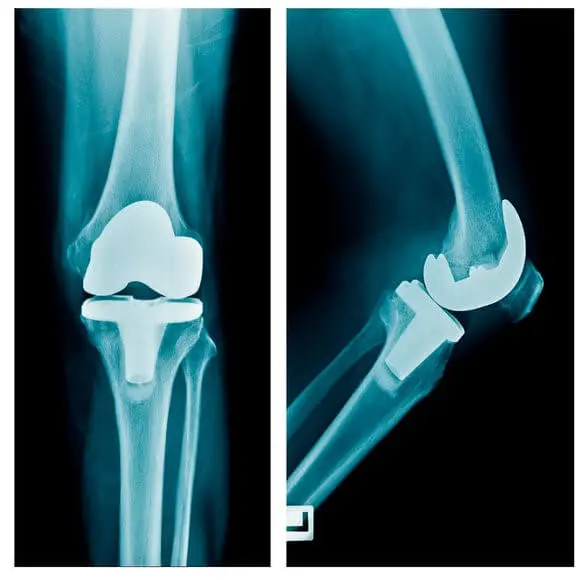

Артроз на поздних стадиях его развития является инвалидизирующим заболеванием. Лечение 3-4 стадии артроза проводится чаще путем эндпротозирования: замены старого «изношенного» сустава на искусственный новый. При полной изношенности сустава – это единственный путь решения проблемы. Но, как любая операция, эндопротезирование имеет свои риски.

Операция эндопротезирования сложная и достаточно травматичная. Эндопротез позволяет двигаться, но ограничивает человека в его привычной двигательной активности. Например, с обычным эндопротезом проблематично иметь исходный (желаемый) объем движений в суставе. Более того, чтобы продолжать с эндопротезом кататься, например, на лыжах, понадобится очень дорогой сустав. И даже с ним будут определенные двигательные ограничения.

Эндопротезирование нуждается в последующем контроле. Например, недогрузка конечности и развитие остеопороза [5] может привести к дестабилизации (расшатыванию) эндопротеза. Поэтому перед операцией эндопротезирования и после нее необходимо пройти денситометрию [6]– исследование плотности костной ткани.

Несмотря на эффективность эндопротезирования в компенсации утраченной функции колена, такое лечение имеет много «подводных камней». . Например, после эндопротезирования боли часто сохраняются. Причины таких болей приходится выявлять при помощи специальных методов меддиагностики. Их устранение требует достаточных усилий по реабилитации, чем активно занимается Центр Меддиагностика. Реабилитация постоперационных болей после эндопротезирования проводится в Центре «Меддиагностика». Поэтому лучше не допустить развитие артроза и стараться сохранить собственный сустав.